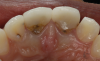

Other clinical situations in which a layered restoration may be indicated instead of a monolithic restoration include when the tooth preparation is discolored, a metal post and core is present, or a metal-based implant abutment is being restored. In these cases, it is advantageous for the crown material to mask the underlying tooth preparation or abutment (Figure 12 through Figure 14).

Fig 12. Discolored mandibular incisors.

Figure 12

Fig 13. Tooth preparations showing dark discoloration

Figure 13

Fig 14. Discoloration masked with layered 3Y zirconia crowns.

Figure 14